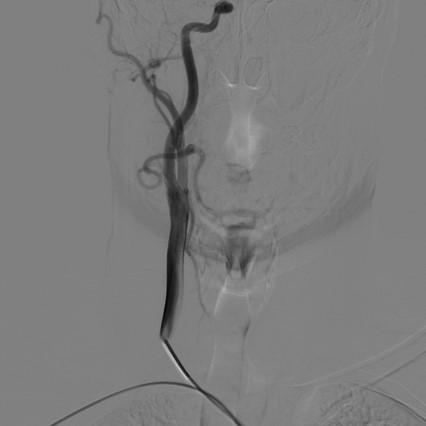

导管超选择右锁骨下动脉